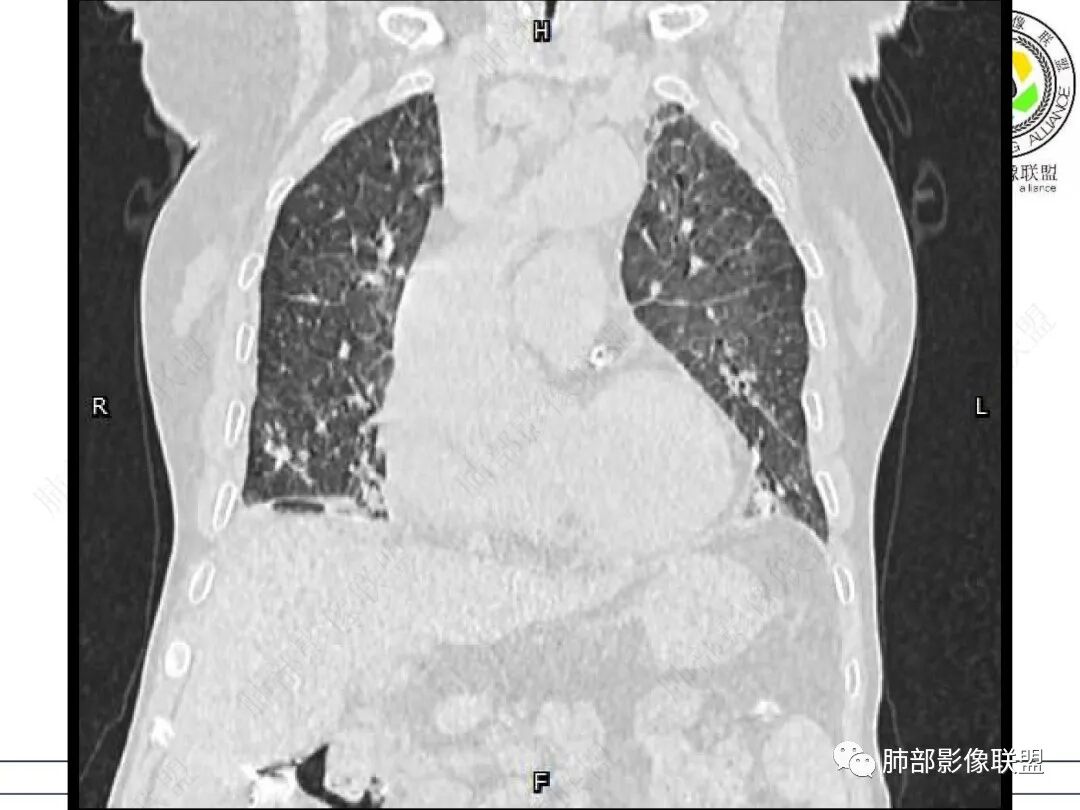

心脏大,胸腔积液,小叶间隔增厚,双肺磨玻璃影,考虑存在肺水肿,另双肺间质性炎性,类风关病史,考虑CTD-ILD,左肺上叶结核可能。

两肺叶后肋膈角区见多发蜂窝状结构破坏表现,双肺叶小叶间隔增厚,左肺上叶后段及舌段和右肺中叶胸膜炎性肉芽肿特点,双侧胸腔少量积液,有类风湿性关节炎治疗史,结缔组织相关性间质性肺病。

老年女性,类风湿关节炎病史多年。发热。以两肺下叶为主弥漫磨玻璃及网格状透亮影,透亮度减低,局部小蜂窝状改变;两肺胸膜下散在几枚实性病灶;双侧胸腔积液。考虑RA-ILDNSIP

女,71,外阴疼痛2周,发热1周。类风关、高血压、高血糖、卵巢囊肿、肠粘连、胆囊结石等病史及相关药物治疗史。胸部CT:两肺弥漫磨玻璃,血管束增粗,两下肺后肋膈角多发蜂窝,对称分布,双侧胸腔少量积液,纵隔窗心脏大血管影明显增宽。考虑混合性病变,CTD-ILD,并肺水肿?并PJP?。

①影像表现复杂:较弥漫间质性改变,对称磨玻璃密度为主,小叶间隔增厚,有一定重力分布趋势,未见明显纤维化,气囊及蜂窝位于肺边缘,未见典型“月弓征”。心脏影增大,双侧胸腔积液。